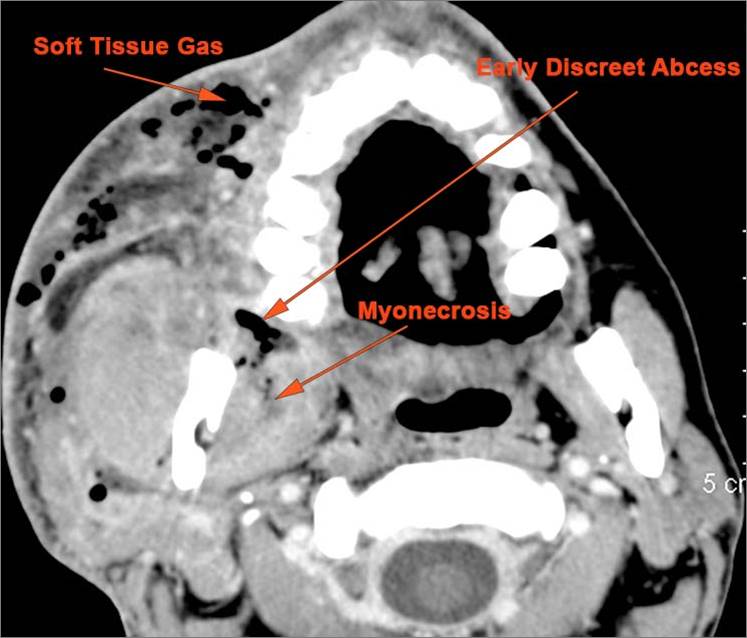

There is general or localized soft tissue swelling of the superficial or deep neck soft tissues. |

Yes | NA |

There is gas in the soft tissues. |

No | NA |

There is edema/abscess arising from the hypopharynx, larynx, thyroid gland or trachea. |

There is edema/abscess within the adjacent deep neck, and/or retropharyngeal space. |